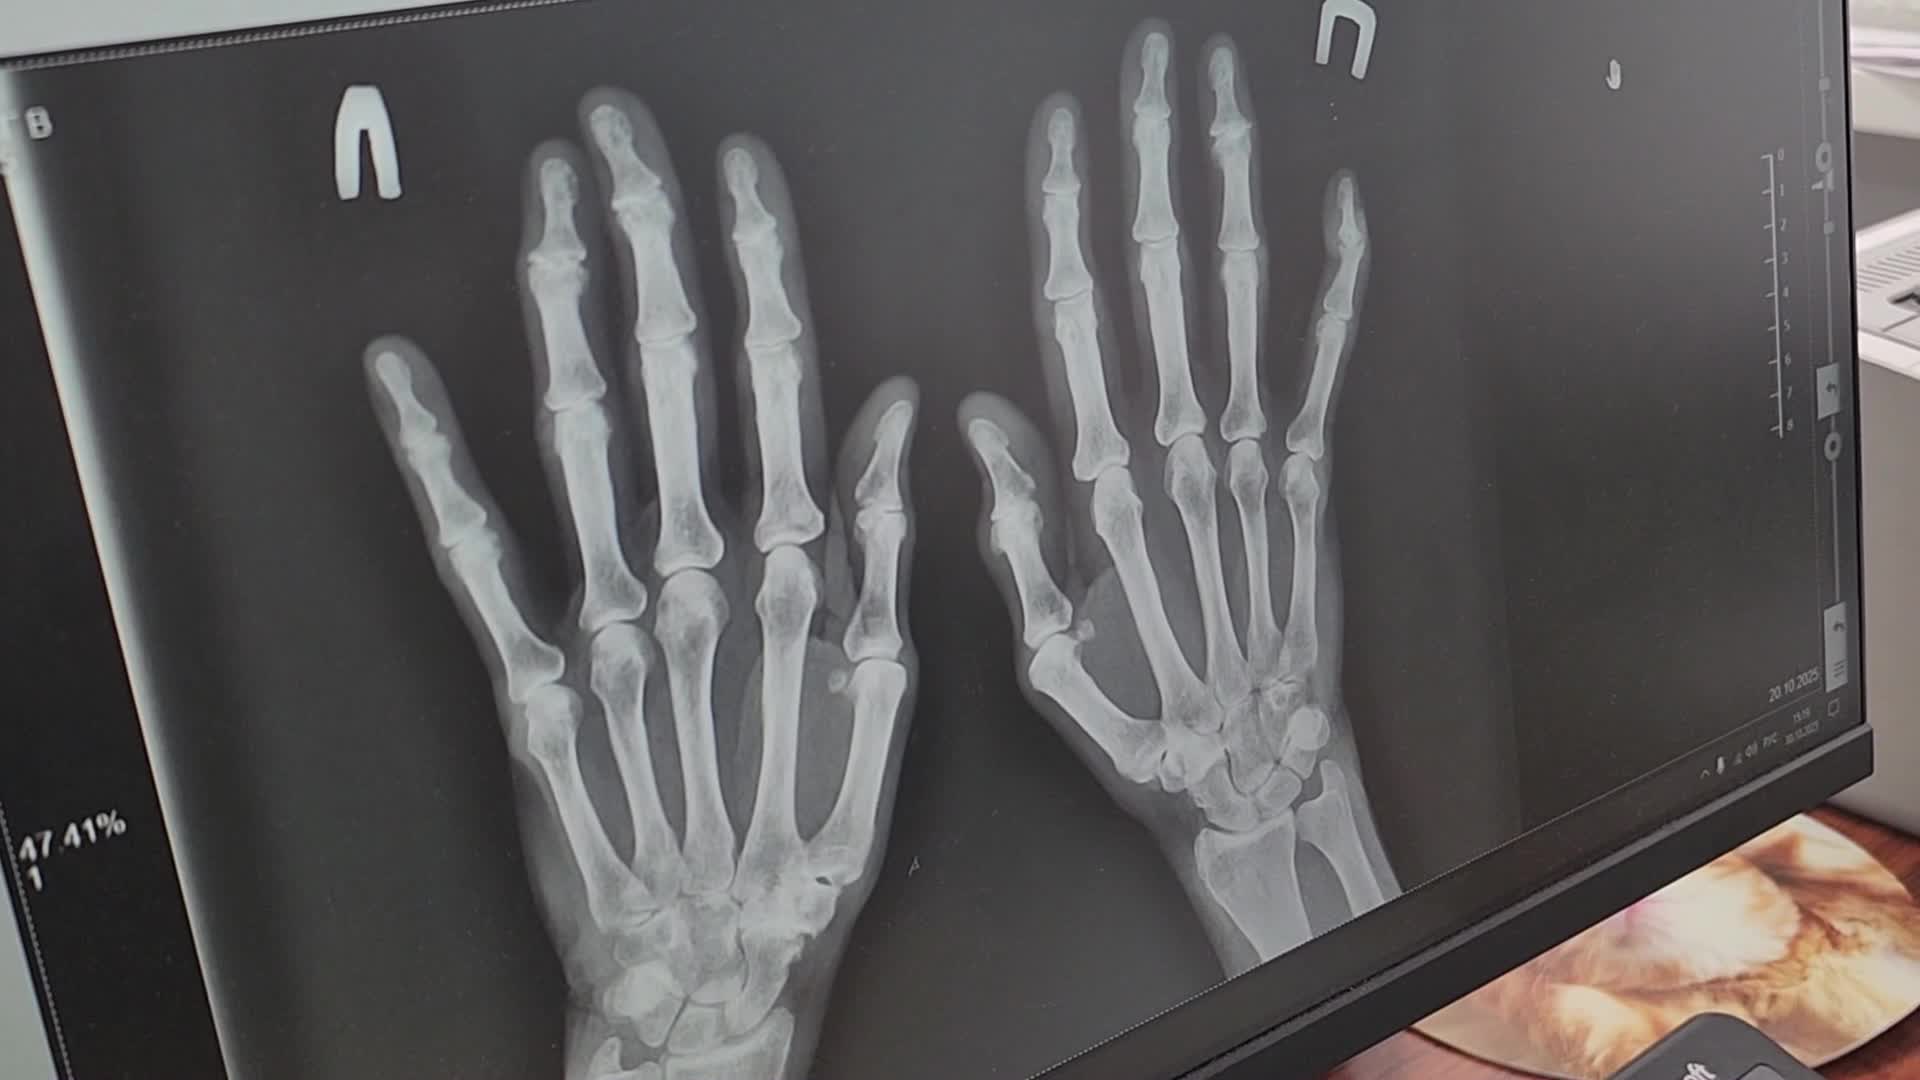

Гигрома — достаточно распространённое доброкачественное образование, представляющее собой заполненную жидкостью кисту. Она часто возникает вблизи суставов пальцев, кисти или запястья. Травматолог-ортопед обособленного подразделения им. М.В. Гольца Щёлковской больницы в городе Фрязино Даниил Лапин рассказал, что эта патология чаще встречается у женщин на лучезапястном суставе. Причины могут скрываться в анатомии — слабые капсулы сустава плюс чрезмерная физическая нагрузка. По статистике от этого заболевания в основном страдают люди ручного труда.